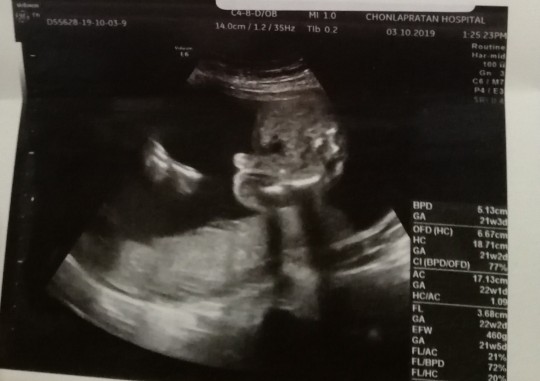

ตอน24wค่ะ